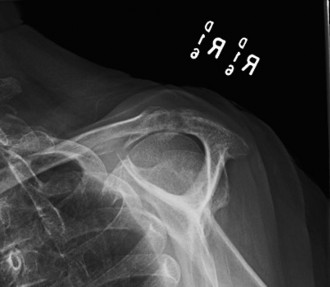

It should be noted that reverse total shoulder arthroplasty is also the procedure of choice in patients with cuff-tear arthropathy (aka rotator cuff arthropathy). Characteristics of cuff-tear arthropathy include superior migration of the humerus due to a massive rotator cuff tear, glenohumeral joint destruction, subchondral osteoporosis, and humeral head collapse (see Fig. 2–17). A reverse total shoulder

Figure 2–17_X-rays of a patient showing evidence of cuff tear arthropathy. The humerus is migrated superiorly, the glenohumeral joint is destroyed, there is subchondral osteoporosis, and the humeral head is collapsed. (From Ecklund KJ, Lee TQ, Tibone J, Gupta R. Rotator cuff tear arthropathy. _J Am Acad Orthop Surg. 2007;15(6):340–349.)